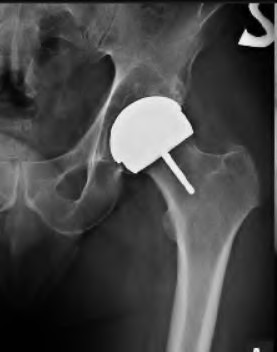

A 35-year-old male presents with right hip pain. MRI confirms avascular necrosis (AVN) of the femoral head. Radiographs show a distinct sclerotic band and cystic changes in the femoral head, but no subchondral collapse or crescent sign. According to the Ficat and Arlet classification, what stage is this, and is core decompression generally indicated?